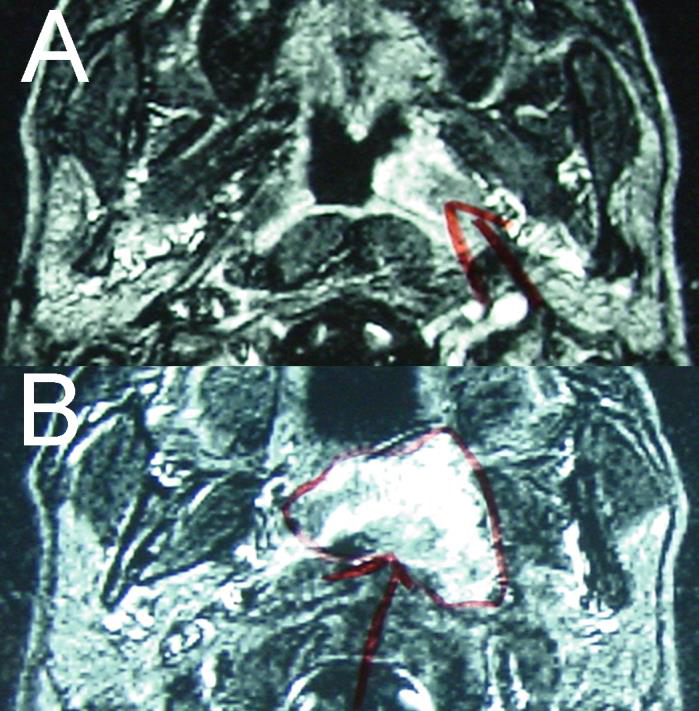

Figure 2: Enhanced T1-weighted magnetic resonance imaging Highintensity area in the left nasopharynx, including the fossa of Rosenmüller (a) and parapharyngeal space (b).

figure 2